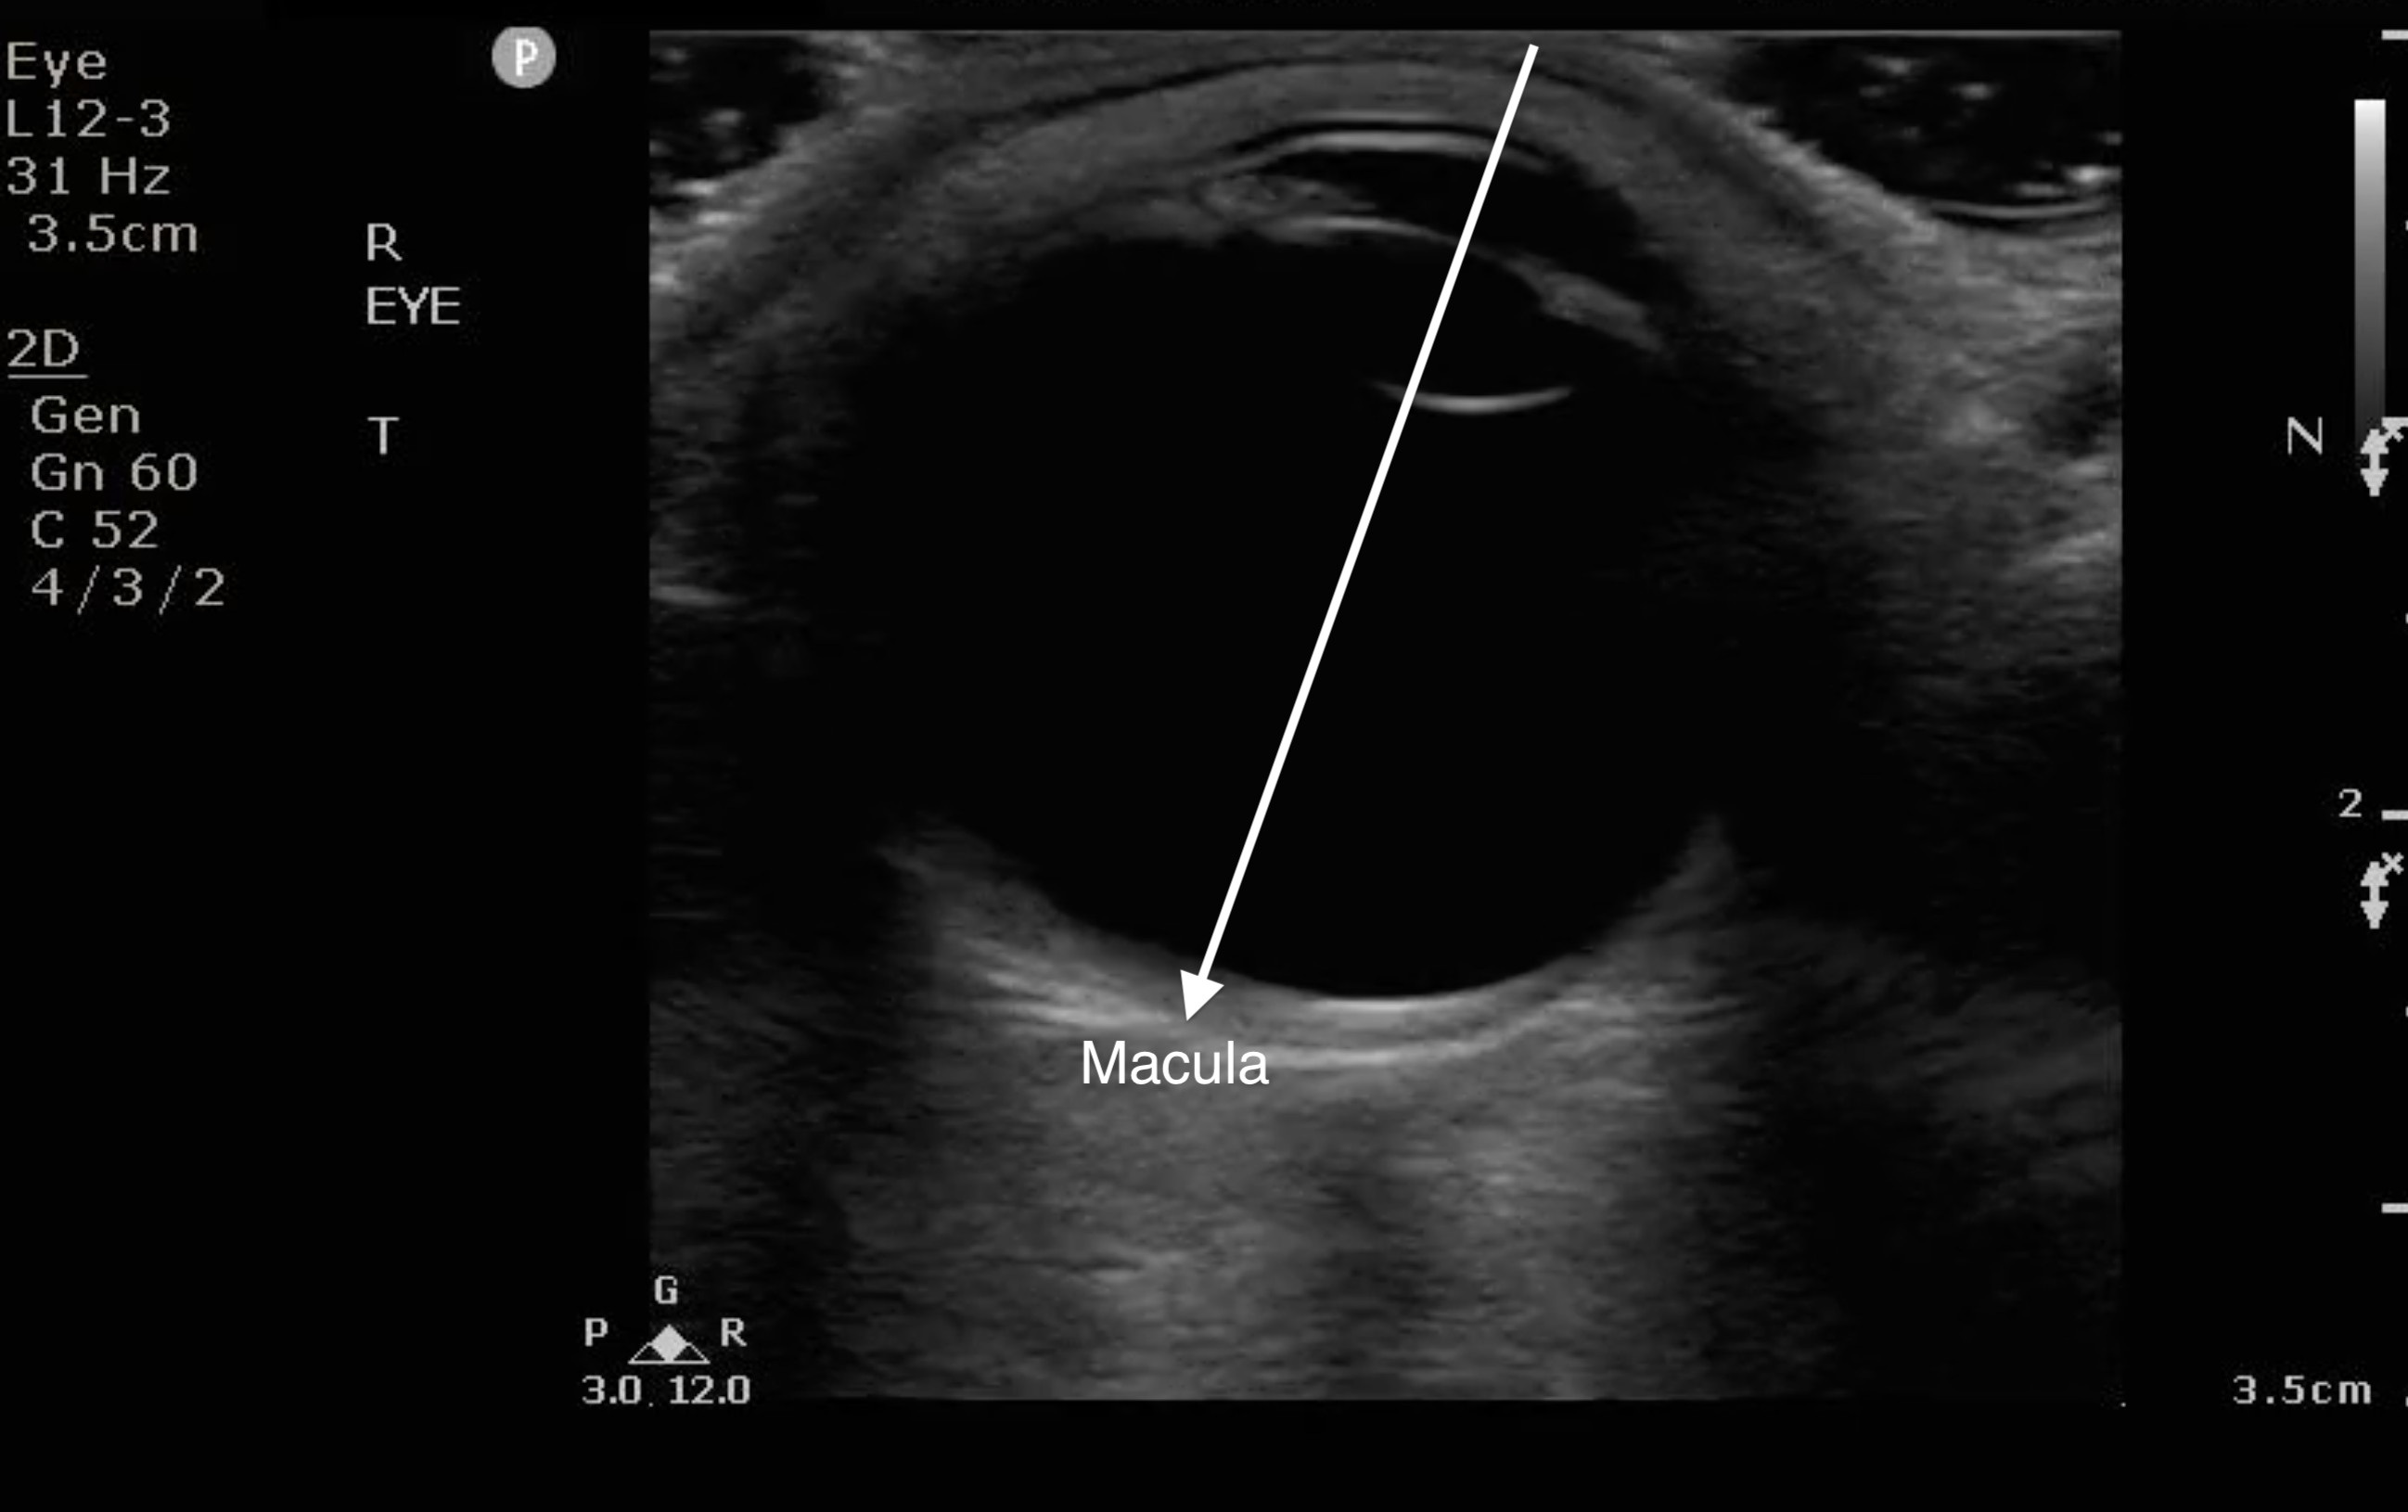

- The macula is temporal to the optic nerve. It cannot be visualized sonographically though location can be approximated by the location of lens (see Fig. 8). If the RD extends temporally from the base of the optic nerve, it can be assumed that it has come off of the macula (“mac off retinal detachment”).

- Figure 8. When the anterior chamber is lined up with the lens, draw a line to bisect the globe to the back on the temporal side. That is where the macula is located.

- RD with the retina still over the macula is an ocular emergency warranting an emergent consultation to ophthalmology in order to take measures to prevent the retina from coming off of the macula.

- RD with the retina off the macula requires an urgent follow-up with ophthalmology.